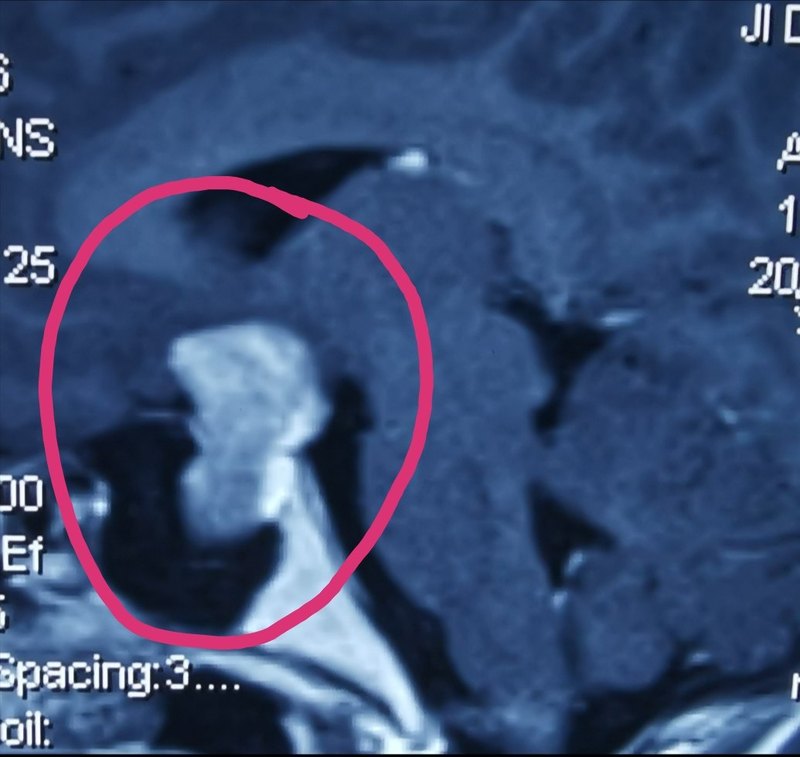

2020年新年第一例垂體瘤患者,家鄉(xiāng)衡陽25歲的小姑娘,在浙江上班,因為閉經(jīng)視力下降發(fā)現(xiàn)垂體巨大腺瘤,想去上海大醫(yī)院就診手術(shù),卻被告知需要等待三個月以上,對于這么巨大的垂體瘤,等待三個月確實不是明智的選擇。 經(jīng)熟人介紹回到家鄉(xiāng)衡陽,術(shù)前準備3天,接受了經(jīng)鼻內(nèi)鏡下微創(chuàng)手術(shù),術(shù)中發(fā)現(xiàn)鞍隔菲薄,繼續(xù)等待有向顱內(nèi)生長風險,那個時候再做,全切率將會降低,術(shù)后腦脊液漏并發(fā)癥發(fā)生率將大大增加。 垂體巨大腺瘤以前被認為是經(jīng)鼻內(nèi)鏡的相對禁忌癥,全切率較低,目前隨著內(nèi)鏡技術(shù)的進步,巨大侵襲性腺瘤的全切率大大提高,并發(fā)癥明顯減少! 垂體瘤的發(fā)病率較高,家鄉(xiāng)人民到大城市就醫(yī)手術(shù)的不在少數(shù),對高質(zhì)量醫(yī)療的需求日益劇增,唯有專注和專業(yè),才能不負重托! 得了垂體瘤,其實不用走遠,家門口就能解決!